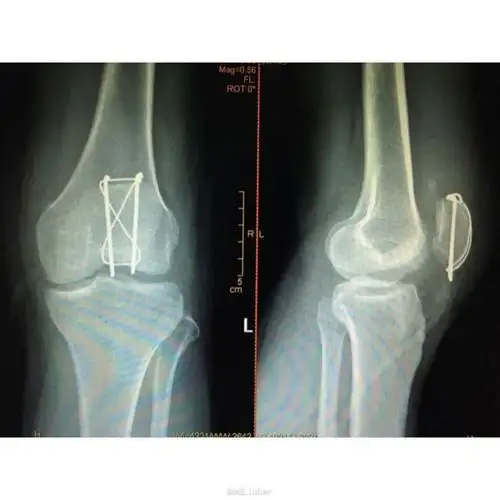

髌骨骨折切开复位克氏针张力带内固定